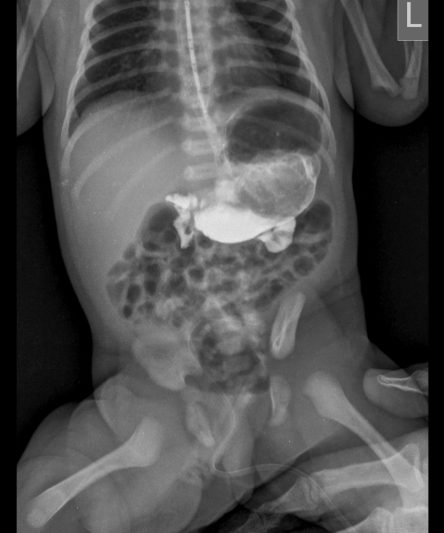

Microskan with Ultra high frequency can take the Lateral Lumbar Spine image of a 90 kg Patient with the correct image receptor

Microskan is the lightest mobile X-ray unit available